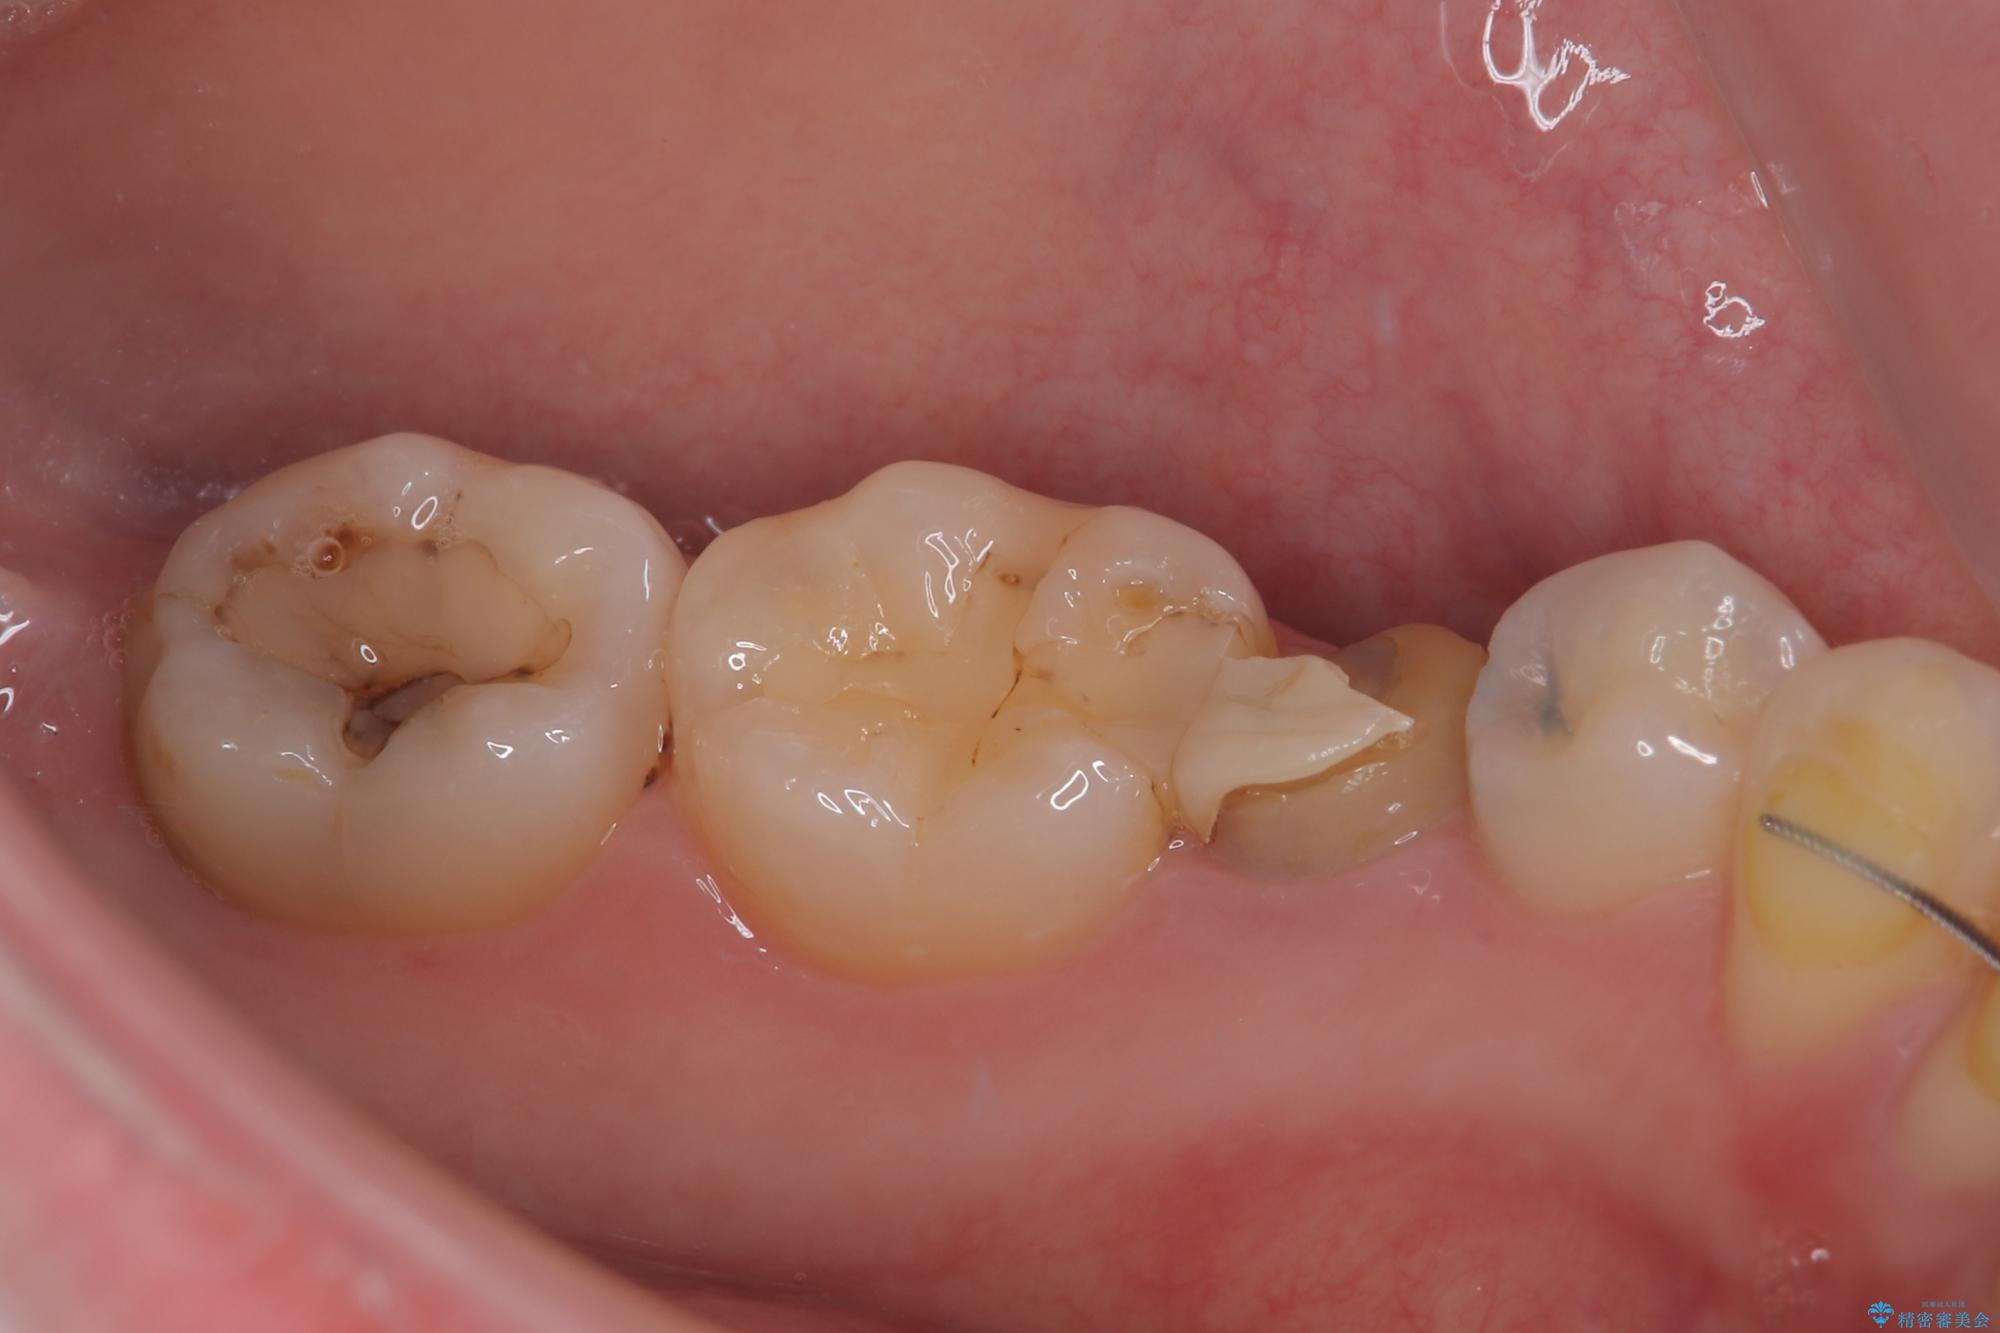

拡大鏡視野下で被せもの、虫歯の除去を行い、オールセラミッククラウン、セラミックインレーに適した形に整えました。

歯と歯茎の間に圧排糸と言われる糸を入れてシリコーン印象材にて精密な型どりをしました。

セラミックインレーの装着時には、唾液の侵入を防ぐために、ラバーダム防湿を行いました。

患者様のご希望により左下5番目の根管治療は行っておりません。